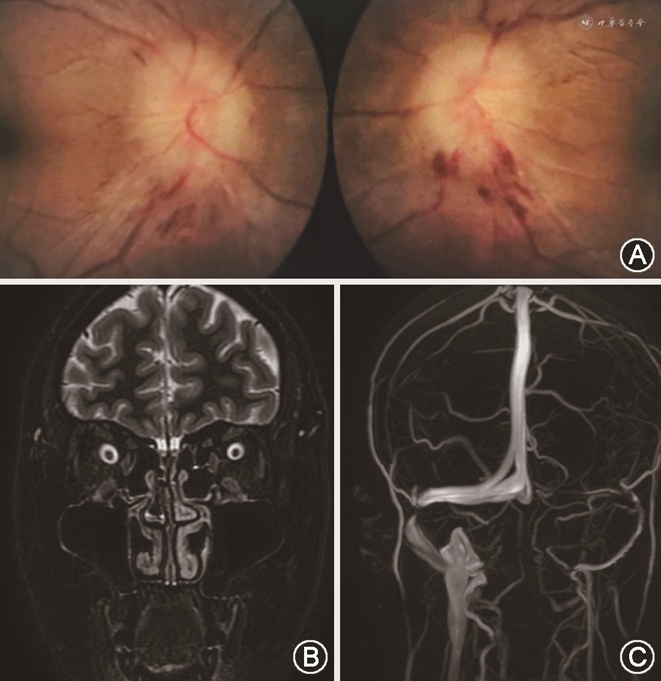

双侧ODS的主要病因的临床特征见表1,典型病例眼底及影像学表现见图2, 3, 4, 5, 6。

2. ON:共40例(40/131,30.5%)。(1)根据病因分类:特发性ON 38例、感染性ON 1例、自身免疫性视神经病1例。特发性ON根据发病机制分型:MOG抗体相关疾病(myelin oligodendrocyte glycoproteinantibody-associated disease,MOG-AD)8例,AQP4阳性视神经脊髓炎谱系疾病(neuromyelitis optica spectrum disorders,NMOSD)3例,自身免疫胶质纤维酸性蛋白(glial fibrillary acidic protein,GFAP)星型细胞病1例,其余26例为抗体阴性的非典型ON。感染性ON 1例的感染病原体为梅毒螺旋体。自身免疫性视神经病1例的原发自身免疫病为白塞病。(2)根据受累部位分类:视神经乳头炎36例、视神经网膜炎4例。

双侧ODS第二常见的病因为ON(30.5%)。以往双侧ODS病因研究中均未提及ON的分型,本研究对ON做了病因分类。典型性ON,也称特发性脱髓鞘性ON,常和多发性硬化相关,1/3患者伴视盘水肿,但多为单眼发病。本研究中双侧ON均为非典型性ON。以往研究表明,MOG抗体阳性的ON患者多双眼受累(约60%)[16],常累及视神经前段,出现视盘水肿者多见(约80%)[16, 17]。而AQP4抗体阳性ON多累及视神经后段、视交叉及视束部位,视盘水肿相对少见(约1/3)。GFAP星形细胞病最常见的表现类型为脑膜脑炎或脑膜脑脊髓炎,双侧ODS在GFAP星形细胞病中发生率为32%,病因更倾向于炎性血管病变导致的视神经乳头炎,而并不是常见的颅内压增高[18, 19]。本研究中,抗体阴性的非典型ON占大多数(65%),ON的未知抗体仍需不断探索和研究。